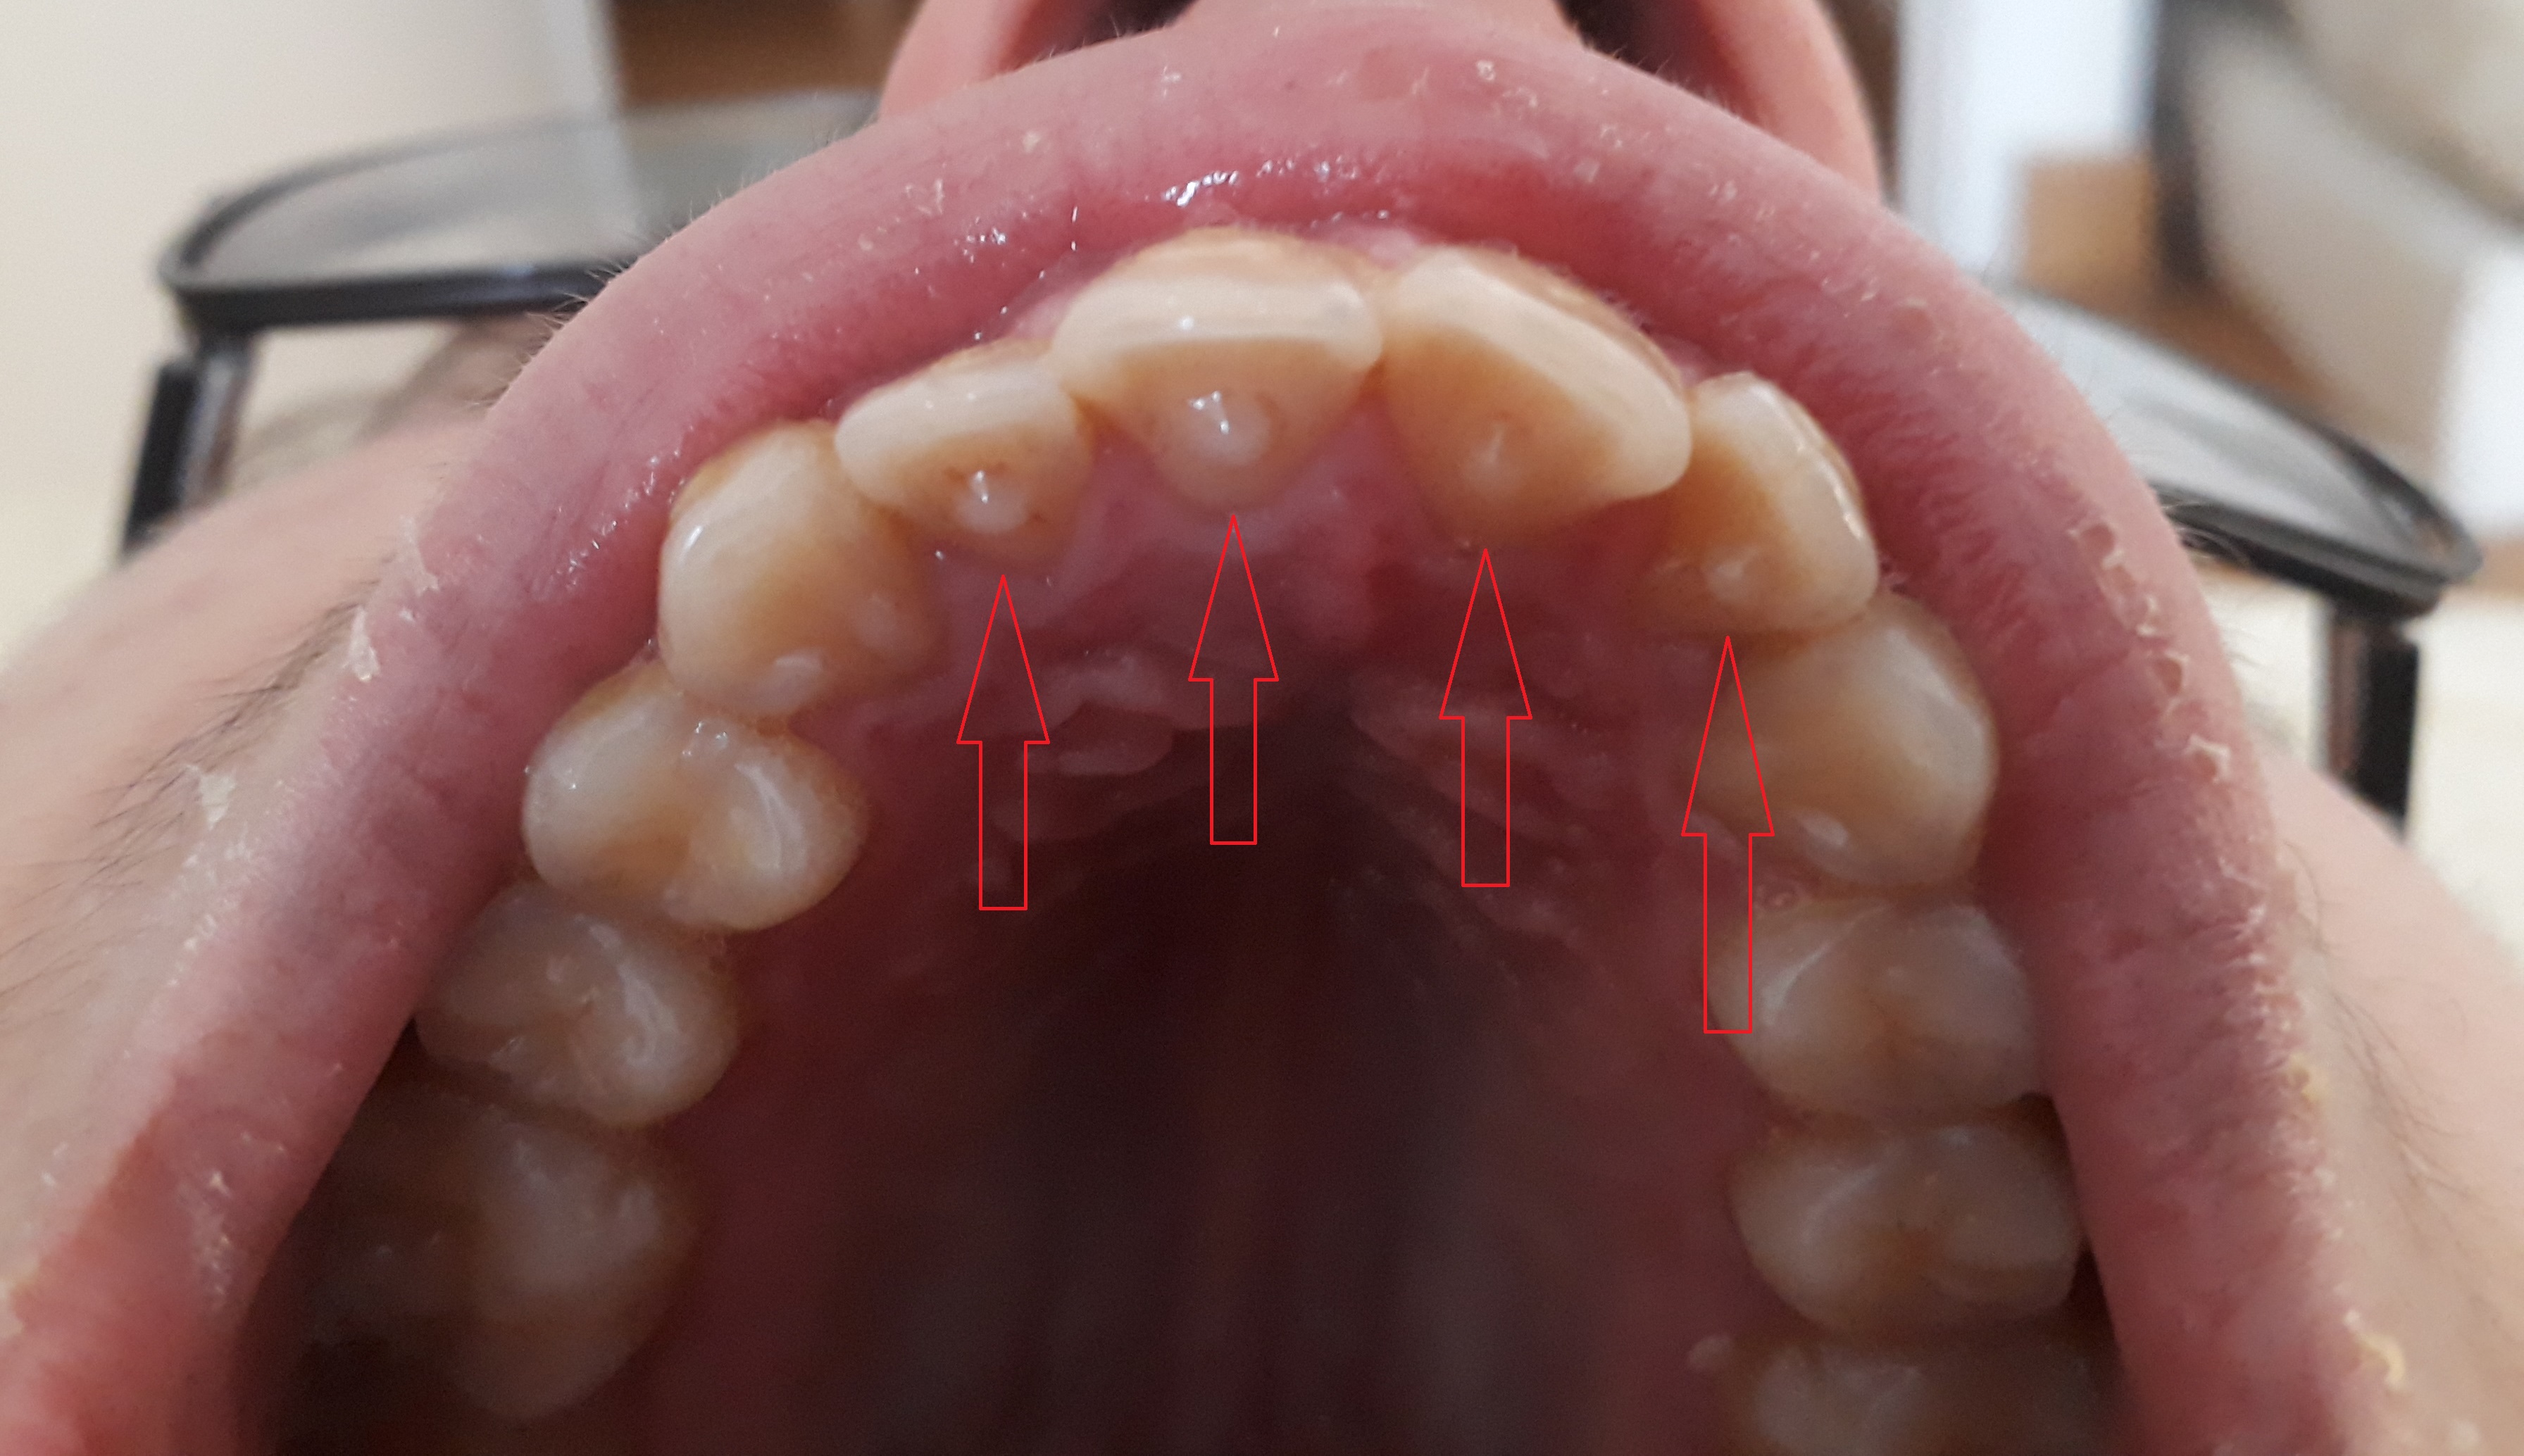

2. Les micro-stimulations dentaires

Le traitement comporte aussi la pose de micro-stimulations sur les dents obtenues grâce au collage de résines de petite taille, moins d'un millimètre (les ALPH®).

Elles sont invisibles et compatibles avec un traitement orthodontique classique.

Lors du traitement, les parents peuvent vérifier de temps à autre la présence des ALPH®.